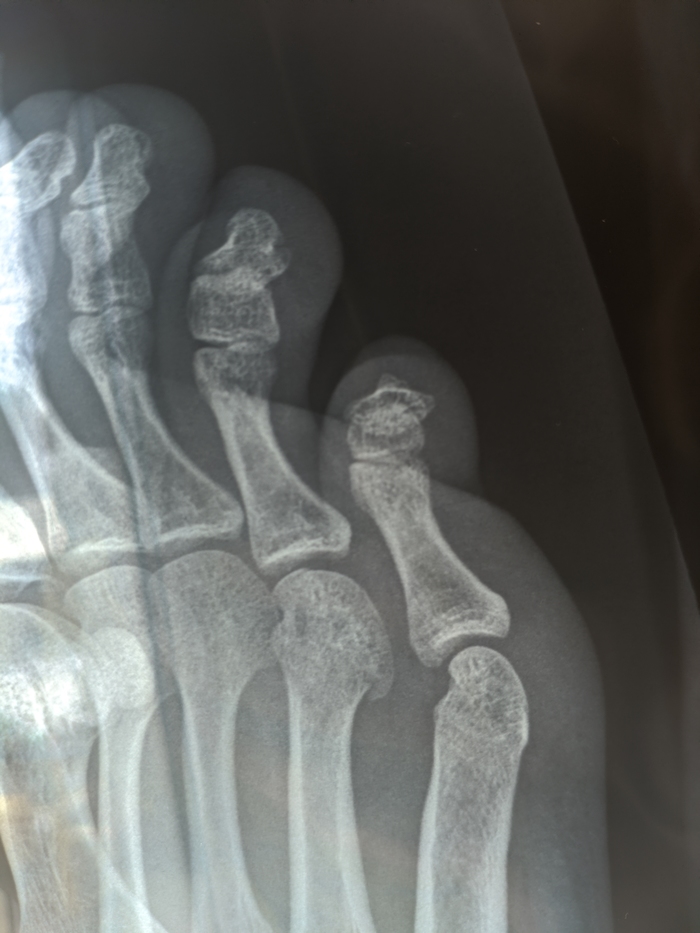

Перелом 4-той плюсневой кости

Упал на лестнице и сильно ударился ногой, больше недели ходил думал арболит да перестанет, но терпимая боль в некоторых положениях не проходила, ходить мог только на пятке. Пошел в травмпункт как итог гипс, лангетка. Может кто так же ломал? Сколько в гипсе ходили?